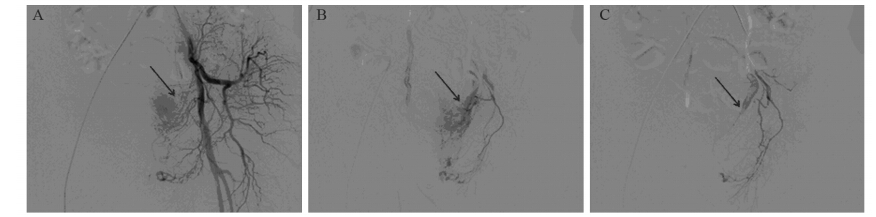

血管造影表现:23例患者,共行28次栓塞治疗,插管造影技术成功率为100%。其中,膀胱上动脉8例、膀胱下动脉13例、阴部内动脉主要参与供血2例。其中,18例患者行超选择性栓塞治疗,5例因超选择性栓塞困难而行髂内动脉栓塞。19例行双侧栓塞和4例行单侧栓塞,动脉期可见肿瘤的供血动脉增粗、迂曲不规则,11例患者实质期造影可见肿瘤染色征,其中19 例双侧髂内动脉分支参与供血,4例主要有一侧髂内动脉供血,2例直接可见对比剂外溢现象。其中1名78岁男性“肉眼血尿3天”就诊患者,栓塞术后造影显示肿瘤区的染色影消失,提示治疗有效,见图 1。

| A: Pre-embolization: increased vascularity demonstrated by left internal iliac images; B: Microcatheter angiography showed increased vascularity in pelvic area; C: Post-embolization: obliteration of blood flow 图 1 高龄膀胱癌患者经导管动脉栓塞术前后微导管造影1例Figure 1 One case of microcatheter angiography on elderly patients with bladder carcinoma before and after transcatheter arterial embolization |